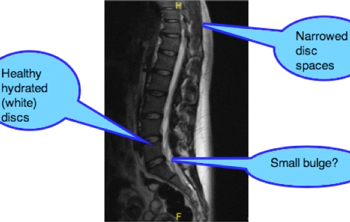

The report that came with the MRI scan stated that it was a normal scan. However, on closer examination, the disc spaces in the upper lumbar spine were noticeably narrower, and the change from the lumbar lordosis, to a thoracic kyphosis was somewhat abrupt.